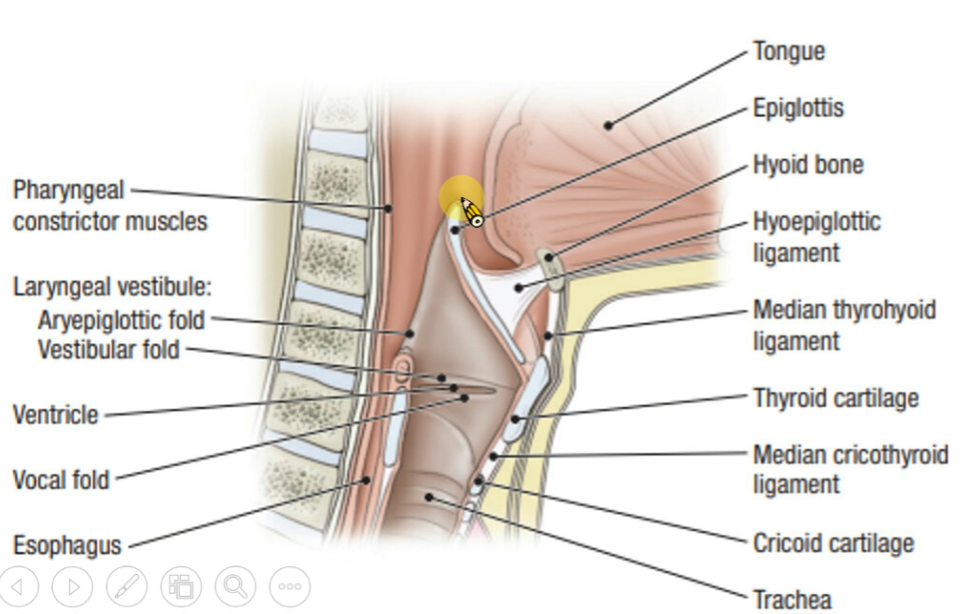

Larynx

假聲帶:Vestibular Fold

Artery

Nerve

- Sup. laryngeal n.

- Internal br.(Internal laryngeal n.)

- Sensor

- 穿過 Thyrohyoid ligament

- External br.

- Motor

- Internal br.(Internal laryngeal n.)

- Recurrent laryngeal n.

- Inf. laryngeal a.伴行

- 過Cricothyroid joint改叫Inf. laryngeal n.